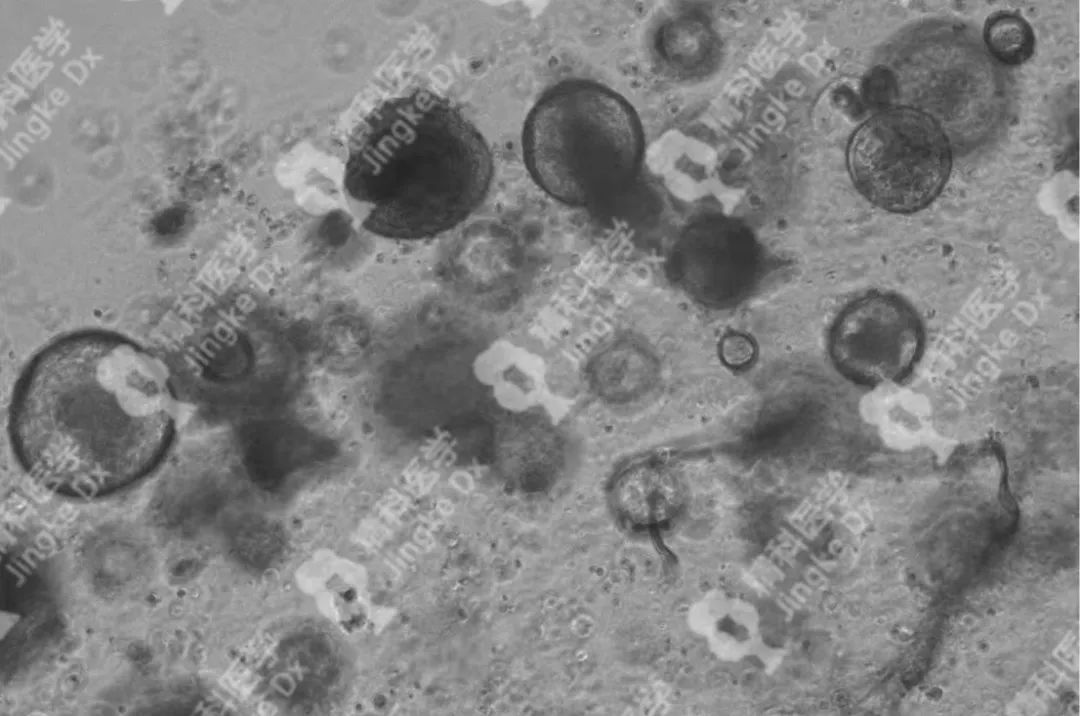

精科類器官培養(yǎng)相關(guān)服務(wù) 精科醫(yī)學(xué)作為類器官技術(shù)轉(zhuǎn)化先行者致力于推動類器官技術(shù)的轉(zhuǎn)化與應(yīng)用,對基于類器官培養(yǎng)擁有成熟的技術(shù)與經(jīng)驗。精科類器官團隊技術(shù)深耕十余年,擁有國內(nèi)頂級的類器官團隊,超微量建模技術(shù)成功率高達95%以上,有成功建模30+種腫瘤的經(jīng)驗(包括上述子宮內(nèi)膜癌、宮頸癌和卵巢癌)??梢蕴峁┌惼鞴俳Ec保存(建模、凍存、傳代)、類器官檢測(類器官H&E染色、免疫組化、藥物敏感度篩選)等多種類器官相關(guān)服務(wù)。檢測服務(wù)最快可在十個工作日內(nèi)完成,更好為患者爭取治療時間。 ★ PIC.01 精科卵巢癌類器官圖像 ★ PIC.02 精科宮頸癌類器官圖像 ★ PIC.03 精科子宮內(nèi)膜癌類器官圖像

★ PIC.04 精科類器官培養(yǎng)其他腫瘤圖像示例